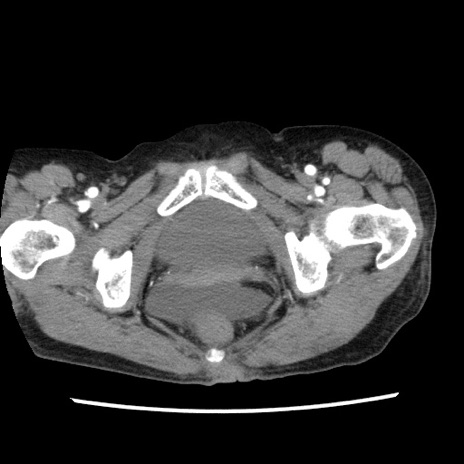

矢状断像